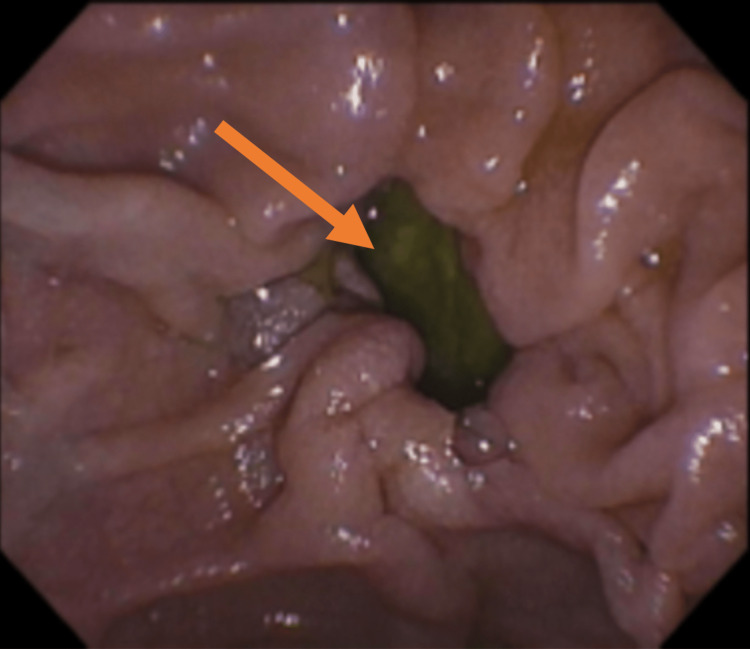

Endoscopy revealed a small duodenal diverticulum, measuring 1 cm × 1.5 cm wide (Figure 1).

Endoscopic retrograde cholangiopancreatography (ERCP) was then attempted, and it was discovered that the major papilla was located entirely within a diverticulum and inverted inside. Multiple attempts to cannulate and readjust the direction of the major papilla were unsuccessful using the ERCP scope and esophagogastroduodenoscopy scope or by clipping the edge of the diverticulum. After the ERCP procedure, the patient was returned to the hospital ward for ongoing care, which included intravenous fluid hydration, a clear liquid diet, laxatives (bisacodyl and miralax/polyethylene glycol), pantoprazole, and heparin for DVT prophylaxis. The patient left the hospital against medical advice before a repeat ERCP could be attempted. She later reported that her symptoms spontaneously resolved.